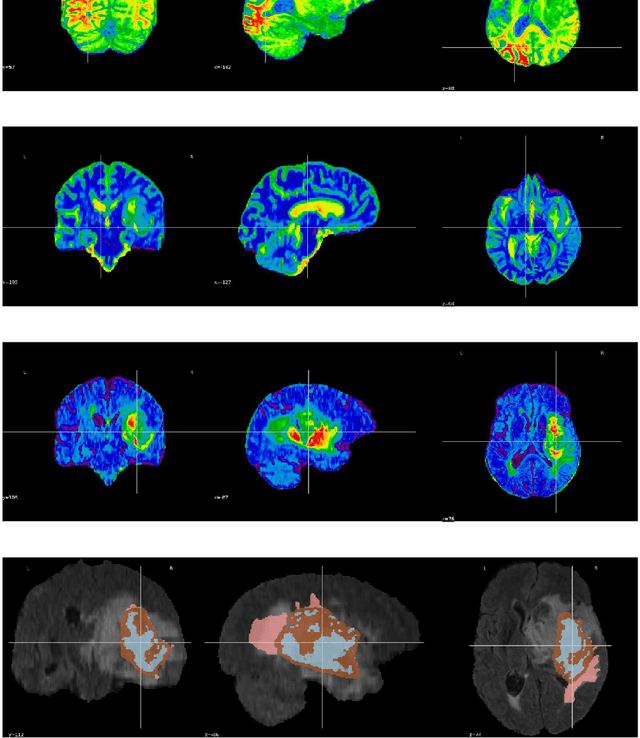

Abstract:Tumors in the brain result from abnormal cell growth within the brain tissue, arising from various types of brain cells. When left undiagnosed, they lead to severe neurological deficits such as cognitive impairment, motor dysfunction, and sensory loss. As the tumor grows, it causes an increase in intracranial pressure, potentially leading to life-threatening complications such as brain herniation. Therefore, early detection and treatment are necessary to manage the complications caused by such tumors to slow down their growth. Numerous works involving deep learning (DL) and artificial intelligence (AI) are being carried out to assist physicians in early diagnosis by utilizing the scans obtained through Magnetic Resonance Imaging (MRI). Our research proposes DL frameworks for localizing, segmenting, and classifying the grade of these gliomas from MRI images to solve this critical issue. In our localization framework, we enhance the LinkNet framework with a VGG19- inspired encoder architecture for improved multimodal tumor feature extraction, along with spatial and graph attention mechanisms to refine feature focus and inter-feature relationships. Following this, we integrated the SeResNet101 CNN model as the encoder backbone into the LinkNet framework for tumor segmentation, which achieved an IoU Score of 96%. To classify the segmented tumors, we combined the SeResNet152 feature extractor with an Adaptive Boosting classifier, which yielded an accuracy of 98.53%. Our proposed models demonstrated promising results, with the potential to advance medical AI by enabling early diagnosis and providing more accurate treatment options for patients.

Abstract:Brain tumors are abnormalities that can severely impact a patient's health, leading to life-threatening conditions such as cancer. These can result in various debilitating effects, including neurological issues, cognitive impairment, motor and sensory deficits, as well as emotional and behavioral changes. These symptoms significantly affect a patient's quality of life, making early diagnosis and timely treatment essential to prevent further deterioration. However, accurately segmenting the tumor region from medical images, particularly MRI scans, is a challenging and time-consuming task that requires the expertise of radiologists. Manual segmentation can also be prone to human errors. To address these challenges, this research leverages the synergy of SeNet and ResNet architectures within an encoder-decoder framework, designed specifically for glioma detection and segmentation. The proposed model incorporates the power of SeResNet-152 as the backbone, integrated into a robust encoder-decoder structure to enhance feature extraction and improve segmentation accuracy. This novel approach significantly reduces the dependency on manual tasks and improves the precision of tumor identification. Evaluation of the model demonstrates strong performance, achieving 87% in Dice Coefficient, 89.12% in accuracy, 88% in IoU score, and 82% in mean IoU score, showcasing its effectiveness in tackling the complex problem of brain tumor segmentation.